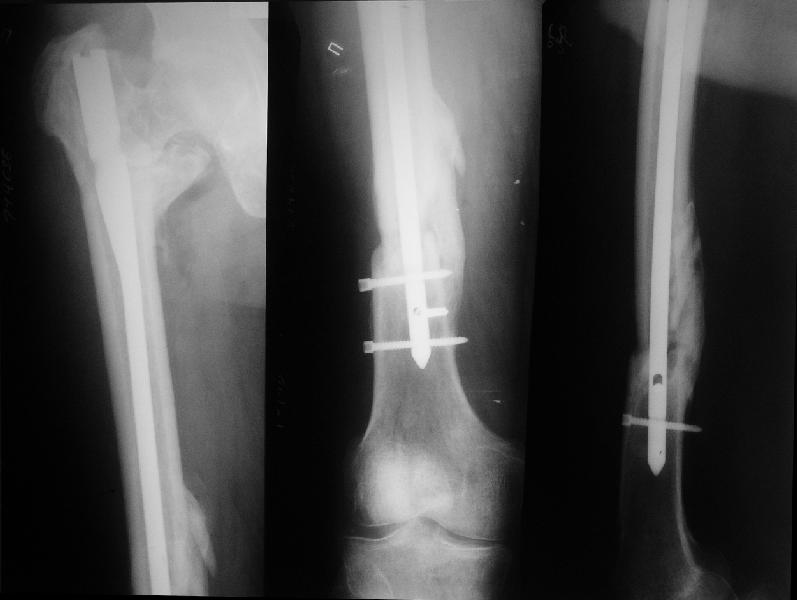

На прошлой неделе оперировали похожего пациента. 2 года после

неудачного остеосинтеза PFN в другом регионе. После удаления остатков

железа выявилось несращение вертельной области.

Поскольку в нашем случае выявилась подвижность, мы наложили дистрактор

таз-бедро на 3 дня, и сделали остеосинтез гаммой без остеотомии. То,

что произошла "корригирующая остеоклазия" в подвертельной области,

выявили после введения гвоздя. Пациент уже уехал домой, будем

наблюдать.